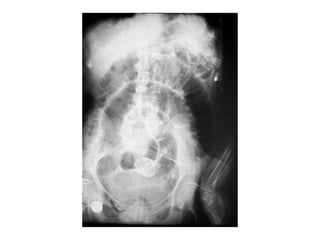

−Intestino grueso: Distribución periférica

• Menor número de burbujas, mayor tamaño y

localización periférica

• Imagen en balón o en arco

• Se observan la haustras

• Ausencia de gas en ampolla rectal en

obstrucciones distales